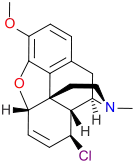

Morphides

- α-Chlorocodide (= chlorocodide)

- β-Chlorocodide

- α-Chloromorphide (= chloromorphide)

- Bromocodide

- Bromomorphide

- Chlorodihydrocodide

- Chloromorphide

- Codide

Structures

| Morphides | ||||

|---|---|---|---|---|

α-chlorocodide α-chlorocodide |

β-chlorocodide β-chlorocodide |

Bromomorphide Bromomorphide | ||

Chlorodihydrocodide. Chlorodihydrocodide. |

Chloromorphide Chloromorphide |

Codide Codide | ||